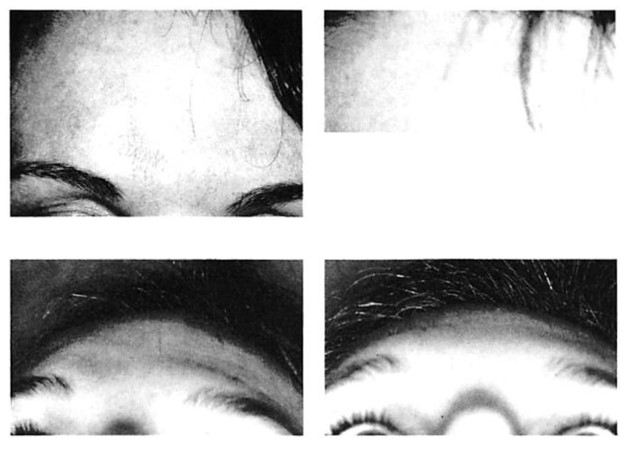

Fig 3. Isolated fracture of anterior wall of frontal sinus in patient with extremely thin soft tissue envelope and prominent frontal sinuses, who was treated with open reduction and internal fixation using microplates and screws. (A) Preoperative frontal view. (B) Postoperative frontal view \ year after surgery shows stable restoration of frontal sinus contour. (C) Preoperative worm’s eye view. (D) Postoperative worm’s eye view. (E) Intraoperative view from above after reduction and fixation with microplates and screws shows extremely low profile of system.

Fig 4. Highly comminuted fracture of supraorbital portion of large frontal sinus that extends to lateral orbit treated with open reduction and microplate and screw fixation. (A) Preoperative axial computed tomographic (CT) scan. (B) Postoperative axial CT shows stable reduction 2 months after injury. Note symmetrical contour of frontal soft tissues.

Fig 4. Highly comminuted fracture of supraorbital portion of large frontal sinus that extends to lateral orbit treated with open reduction and microplate and screw fixation. (A) Preoperative axial computed tomographic (CT) scan. (B) Postoperative axial CT shows stable reduction 2 months after injury. Note symmetrical contour of frontal soft tissues.